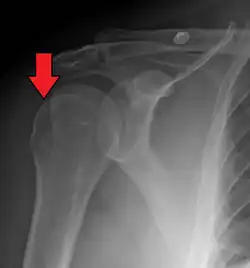

| Anterior shoulder dislocation on X-ray with a large Hill–Sachs lesion | |

A Hill–Sachs lesion, or Hill–Sachs fracture, is a cortical depression in the posterolateral head of the humerus. It results from forceful impaction of the humeral head against the anteroinferior glenoid rim when the shoulder is dislocated anteriorly.

Diagnosis can be suspected by history and physical examination which is usually followed by imaging. Because of the mechanism of injury, apprehension of anterior dislocation is common with provocative maneuvers. Hill–Sachs lesions have been classified as "engaging" or "non-engaging", with engaging lesions defined by the ability of the glenoid to sublux into the humeral head defect during abduction and external rotation. Engaging dislocations have a higher risk of recurrent anterior dislocation, and their presence can help guide surgical management.[2] Imaging diagnosis conventionally begins with plain film radiography. Generally, anteroposterior (AP) radiographs of the shoulder with the arm in internal rotation offer the best yield while axillary views and AP radiographs with external rotation tend to obscure the defect. However, pain and tenderness in the injured joint make appropriate positioning difficult and in a recent study of plain film x-ray for Hill–Sachs lesions, the sensitivity was only about 20%. i.e. the finding was not visible on plain film x-ray about 80% of the time.[3]

The incidence of Hill–Sachs lesion is not known with certainty. It has been reported to be present in 40% to 90% of patients presenting with anterior shoulder instability, that is subluxation or dislocation.[8][9] In those who have recurrent events, it may be as high as 100%.[10] Its presence is a specific sign of dislocation and can thus be used as an indicator that dislocation has occurred even if the joint has regained its normal alignment. Large, engaging Hill-Sachs fractures can contribute to shoulder instability and will often cause painful clicking, catching, or popping. The average depth of Hill–Sachs lesion has been reported as 4.1 mm.[11]